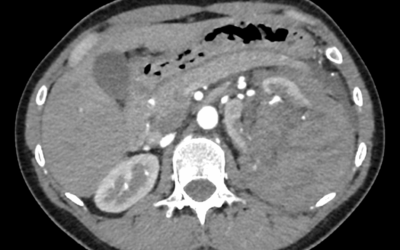

Caso de abdomen

Varón de 80 que consulta por dolor en hipocondrio izquierdo de dos meses de evolución y sensación de masa. El dolor aumenta ligeramente con la inspiración profunda.Comenta pérdida de peso hace 5 años que no ha progresado.Exploración Física: Abdomen blando y...